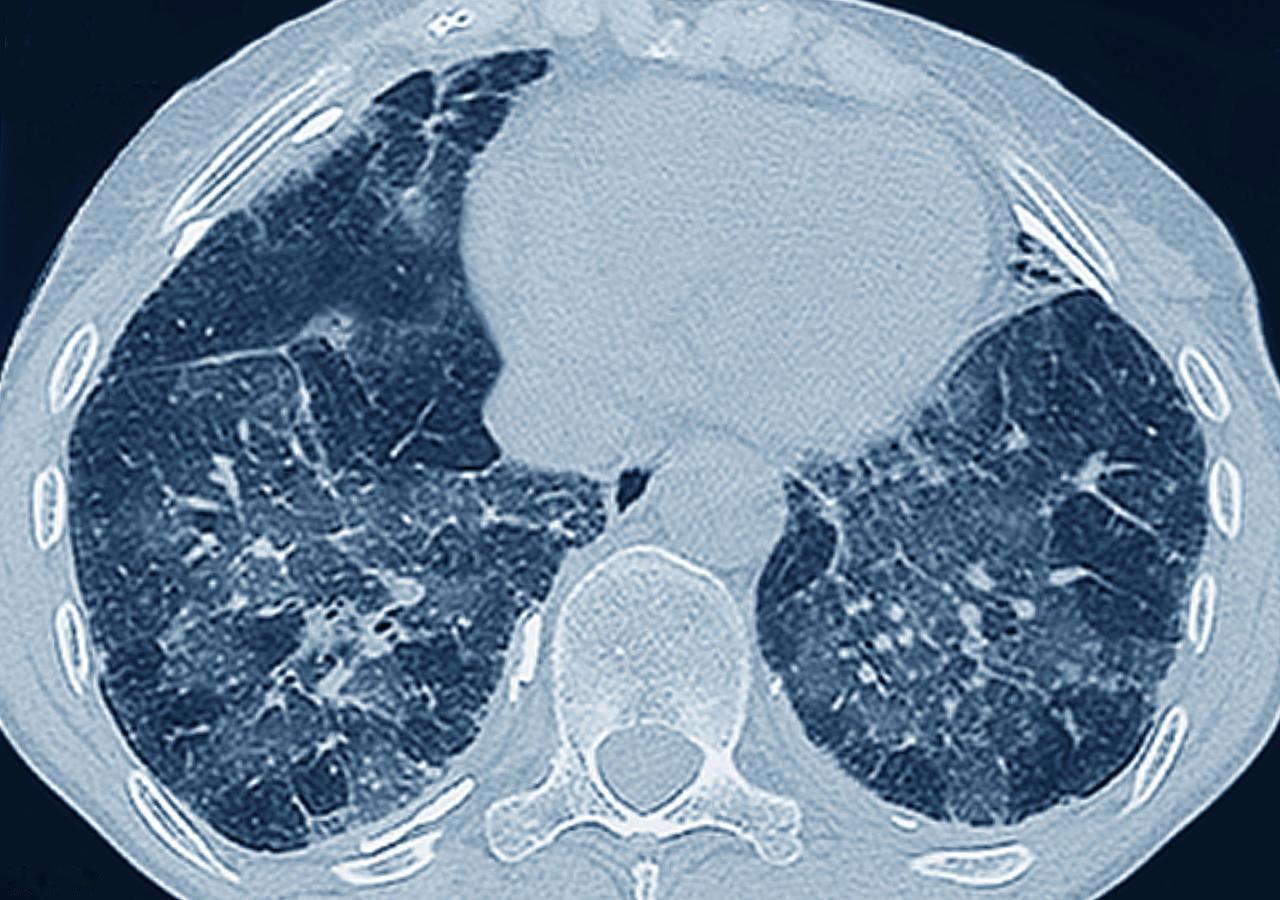

比肺癌更可怕的5个肺部疾病,有的时候来不及抢救,甚至导致猝死 终末期的慢阻肺,慢阻肺是吸烟等病因导致的肺部疾病,如果进入呼吸衰竭的终末期,治疗困难,而且人受折磨 第二就是肺栓塞,肺部大的血管被堵塞,会导致肺部坏死,甚至导致呼吸循环衰竭,严重时会导致猝死,来不及抢救 第三是进入加重期的特发性肺纤维化。特发性肺纤维化本身是一个难以逆转的疾病,当病情进入突然加重的状态,可能会迅速的导致呼吸衰竭。药物使用效果差,这个时候只有肺移植能够挽救生命 第四血液抗MDA5阳性的间质性肺病,MDA5可以说是一个死亡信号。这个指标升高的话,65%的患者会在半年内死亡。主要的表现就是肺部硬化变成间质性肺病,甚至白肺。很难抢救 第五是呼吸窘迫综合症。这个是多种的严重的肺部疾病导致的共同表现。肺会失去通气和换气功能,迅速产生呼吸衰竭的表现,抢救比较困难。有时候需要气管插管,机械辅助通气挽救生命,甚至需要ecmo来维持生命。